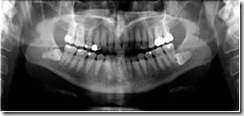

標準パノラマ撮影

標準的なパノラマ画像です。顎の形状とサイズの組み合わせによって9つのパノラマ軌道が得られます。 水平・垂直方向の拡大率1.2倍の均等な画像が得られます。

また、画像管理ソフト上で、精度の高い寸法の計測が可能です。

照射範囲を狭くする事で、患者さんの被曝線量を約35%低減いたします。 お子さんのX線撮影を気にされる方も安心して撮影できます。